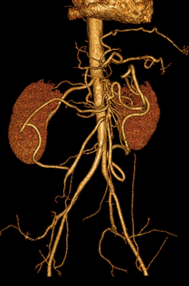

Digestif DES BASE

L’essentiel sur l’ischémie intestinale aiguë en imagerie

DANSE E. - UCL